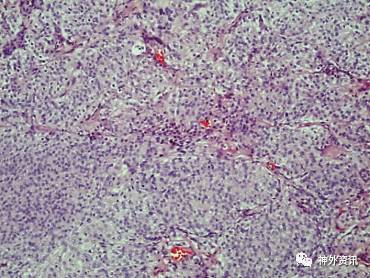

患者接受右额顶叶肿瘤全切除术。手术标本的组织病理学检测提示,I级脑膜瘤(图4、5),证实了SPECT的诊断。术后患者恢复良好,随访期间未发现肿瘤复发。

图4. HE染色(× 10)示:肿瘤细胞形成小叶,被菲薄的胶原隔膜分开。

图5. HE染色(×40)示:肿瘤细胞大小均一,核椭圆形,染色质细,偶见中央清除区或核包涵体;有沙粒小体存在。